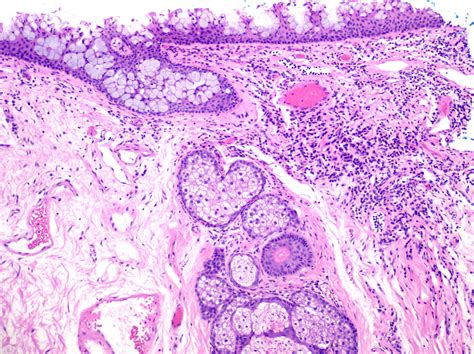

The limbus is a critical structure in the eye, serving as a junction between the transparent cornea and the opaque sclera. It is rich in blood vessels and nerves, which supply the cornea with essential nutrients and oxygen. The limbus is also home to the limbal stem cells, which are responsible for the continuous regeneration of the corneal epithelium. These stem cells are crucial for maintaining the transparency and health of the cornea.

Limbal stem cells are located in the basal layer of the limbal epithelium. These cells have the unique ability to differentiate into various types of corneal epithelial cells, ensuring that the cornea remains clear and free from opacities. The limbus acts as a reservoir for these stem cells, providing a constant supply of new cells to replace those that are lost or damaged. This regenerative capacity is essential for maintaining the integrity of the cornea and preventing conditions such as corneal blindness.